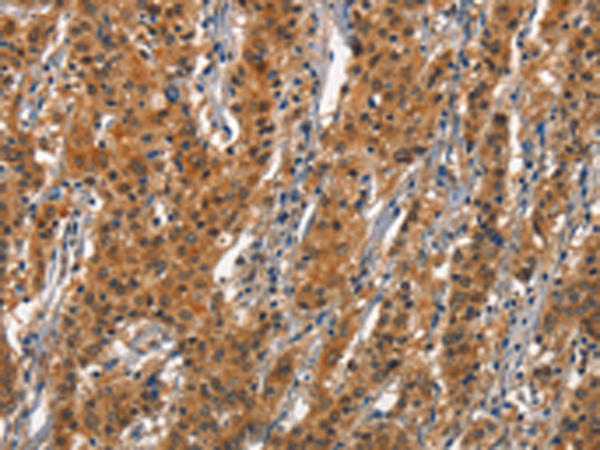

- The image is immunohistochemistry of paraffin-embedded Human gasrtic cancer tissue using P04339(CD163 Antibody) at dilution 1/30. (Original magnification: ×200)